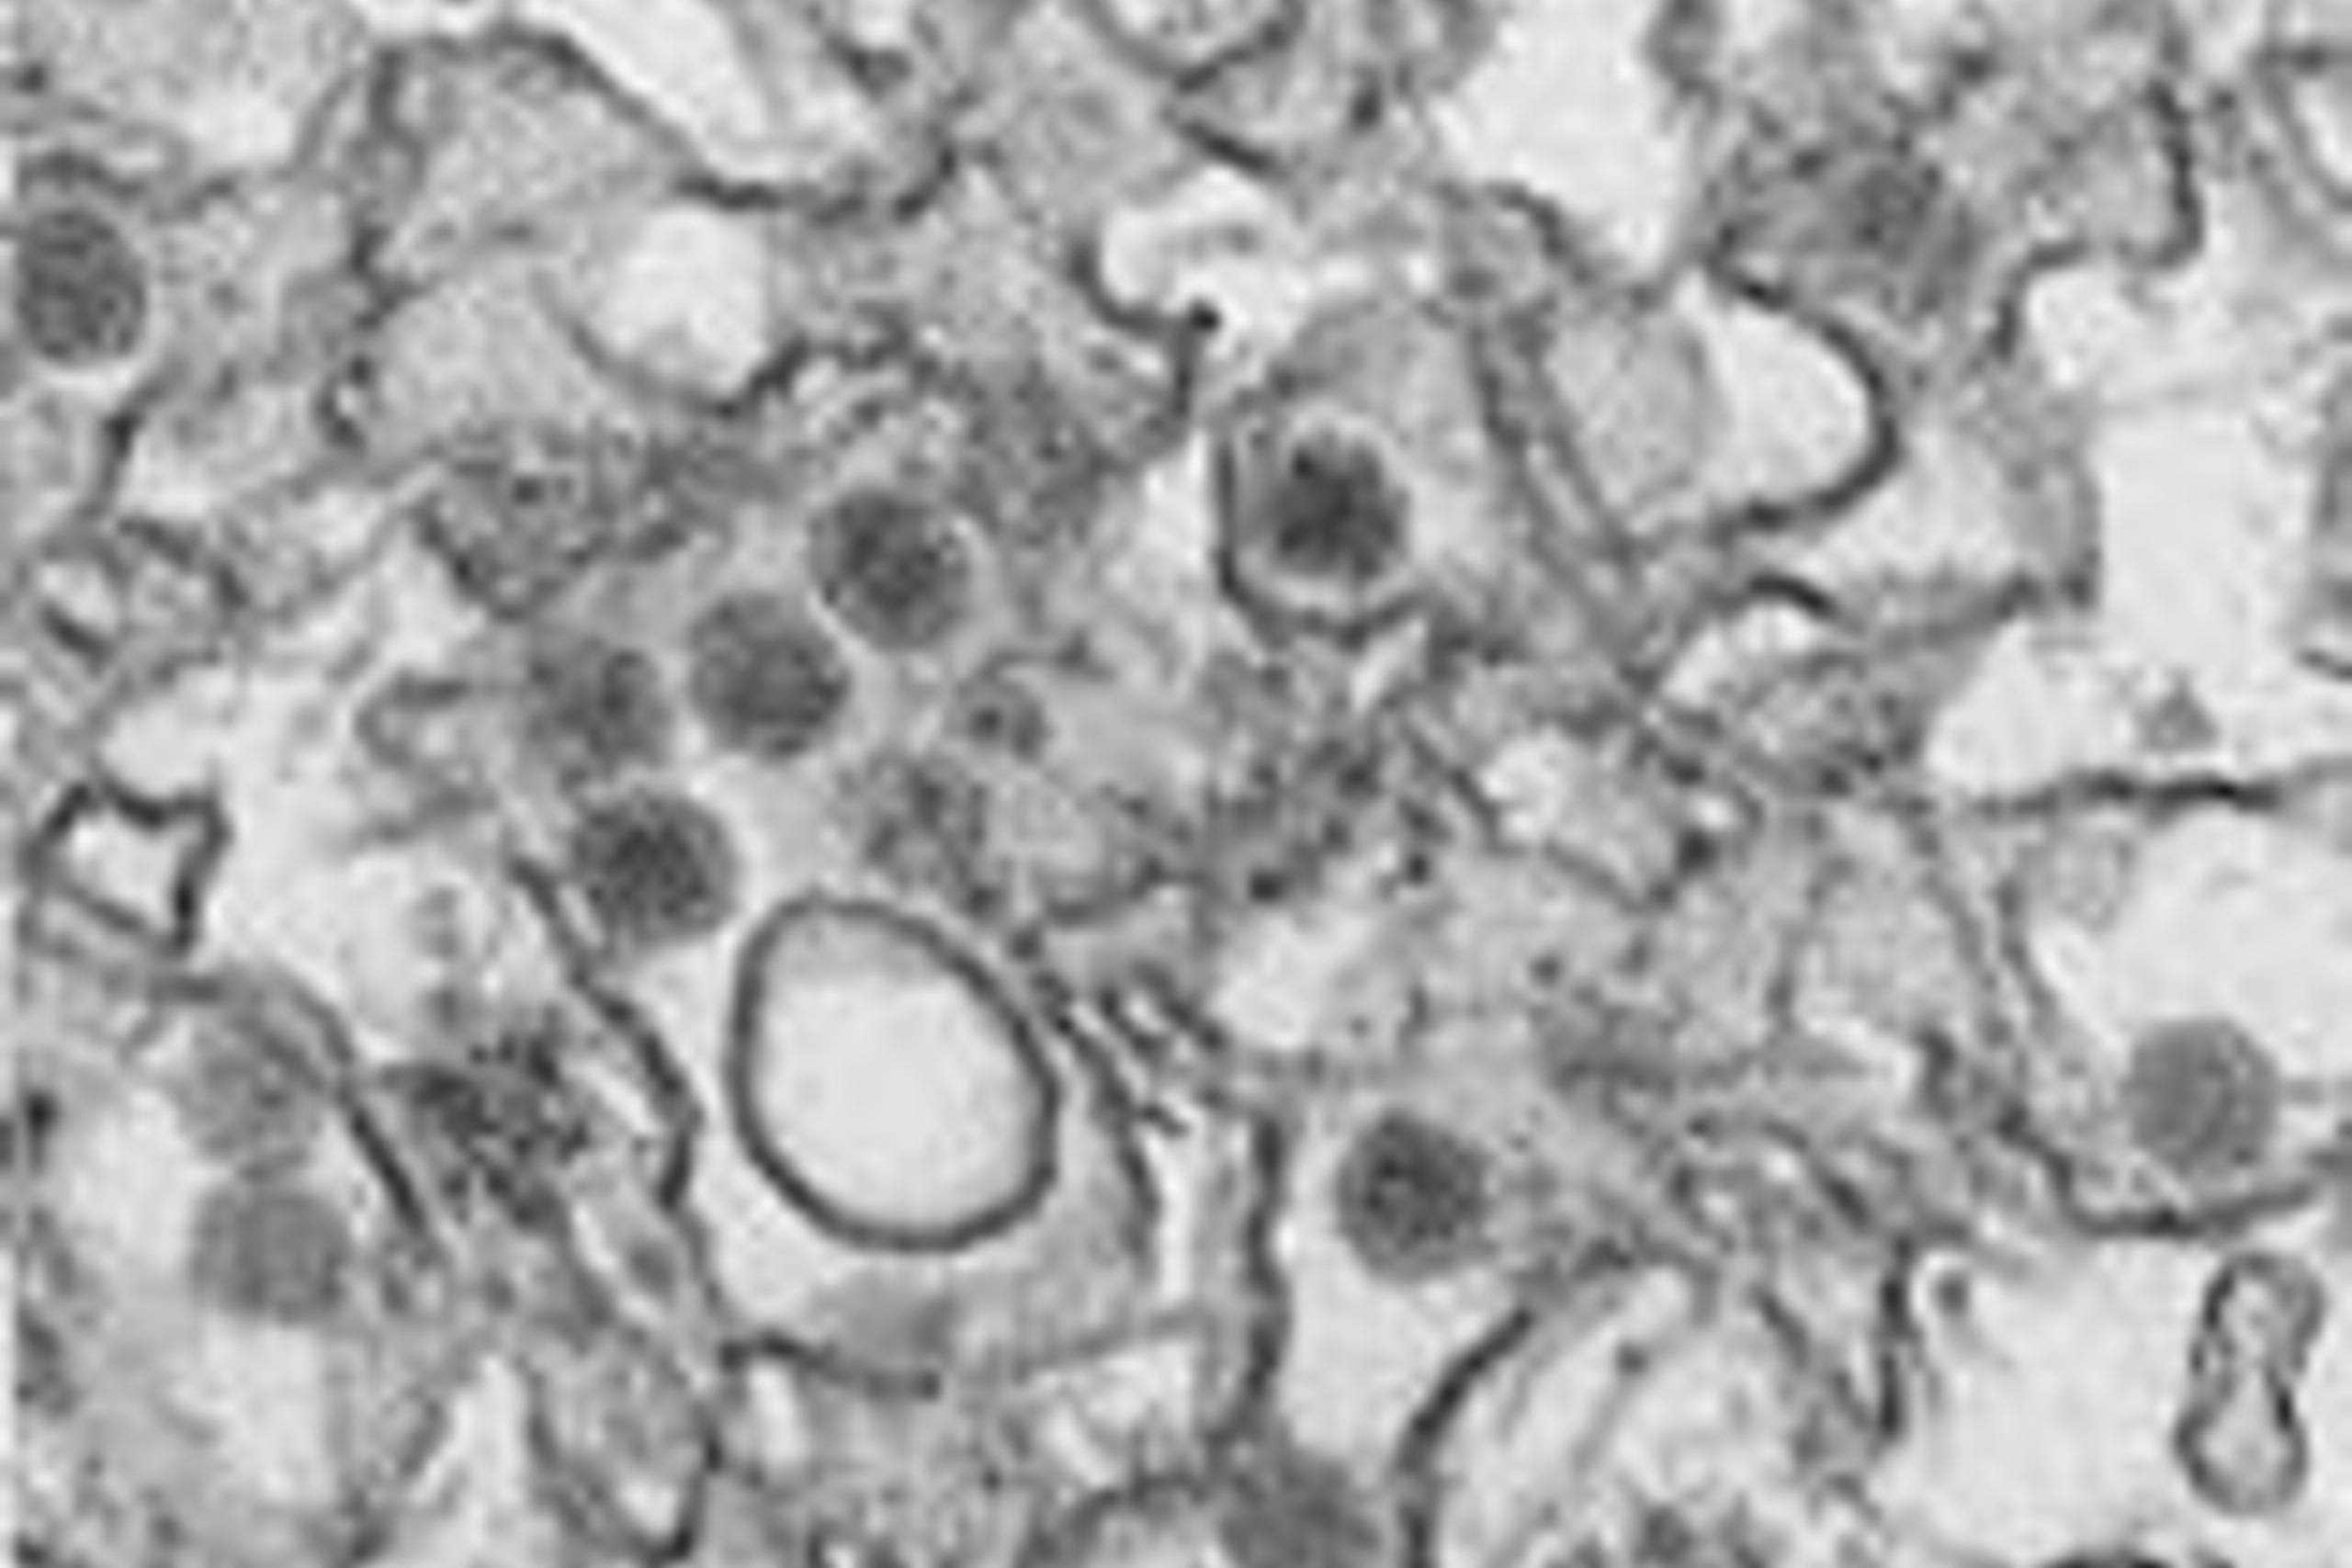

19. jun. 2016InternationalHun ville være gravid: Fandt ud af, at ønskebarnet sandsyligvis er skadet efter zikavirus

19. jun. 2016InternationalKamp mod zika: Mange detaljer skal på plads for at slippe for de forbandede zikamyg